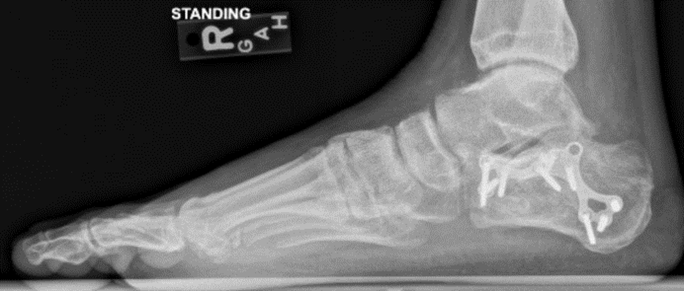

Treatment depends on the type of fracture sustained. The majority of forefoot fractures are mild and do not require surgery. Nonsurgical treatment includes rest, ice, compression, and elevation of the foot. Your provider may suggest a splint, cast, or boot immobilize the foot. For more severe fractures, surgery is usually required to align and reconstruct the affected bones or fuse the damaged joints. The surgical procedure may involve holding together bone fragments with plates and screws.